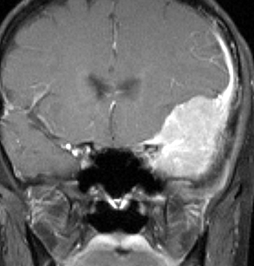

典型的な髄膜腫

この髄膜腫は中程度の大きさのものです。円蓋部髄膜種という最も多い最も手術の簡単なタイプです。麻痺や失語症やてんかんなどの症状はありません。とても美しくて若い女性の髄膜腫でしたが,子供に遺伝はしませんし,癌などと違ってタバコなどこれといった原因がなくて発生するものです。

MRIでの髄膜腫の見え方は撮影の仕方によっていろいろです。左からT1強調画像,T2強調画像,フレア画像といいます。腫瘍の横に小さく白い領域がありますが,これは脳の腫れた部分で脳浮腫といいます。髄膜腫があると周囲に脳浮腫が生じることがあります。

最も見やすいのが,ガドリニウム造影剤を注射して撮影するものです。一般的に髄膜腫は造影剤で白く映し出されます。この腫瘍は左脳側にあります。MRIの軸面という輪切りの写真では左右が逆になりますから注意してください。脳を下から見た図になっています。MRIはいろいろな方向から腫瘍を見ることができますが,右は冠状断という正面から見た図です。よく見ると腫瘍の上と下のはじっこに線状に糸を引いたように造影される部分があります。これをテールサイン(しっぽのサイン)といいます。腫瘍が硬膜に沿って延びている可能性があることを示しています。